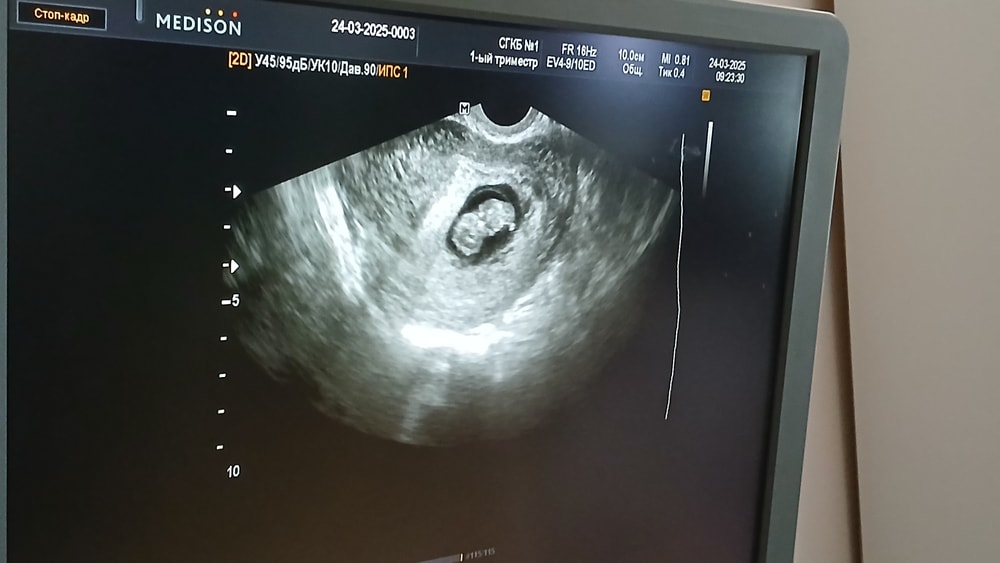

Беременность- 1 триместр ( только до 10 недель)Выписали из больницы,наконец я дома!! С малышариком всё хорошо🥰 но там поймала легкое орви.. активно промываю нос,лечусь,и чай с лимоном,полощу горло))

Малыш так подрос за неделю... пытаюсь понять-где голова,а где низ😁😆

Мне кажется голова внизу, и ручки с ножками даже видно ))) Какой у вас ктр?

Ксения, сегодня у меня по месячным 8+5,по ктр 8+6, и ктр 23мм))